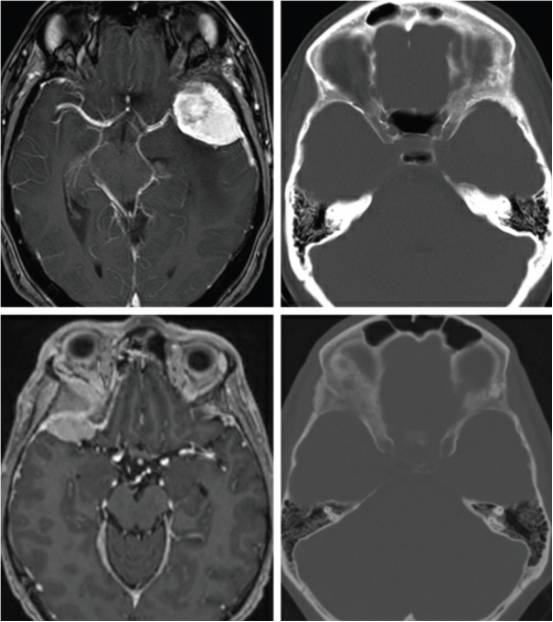

图1. 上图为一个典型的左侧外侧蝶骨嵴脑膜瘤伴骨质增生。下图为右侧蝶眶脑膜瘤伴显著的蝶骨嵴、床突和眶壁增生,导致眼球突出。为长期的控制肿瘤并改善眼球突出,有必要同期切除硬膜内肿瘤和增生的骨质。